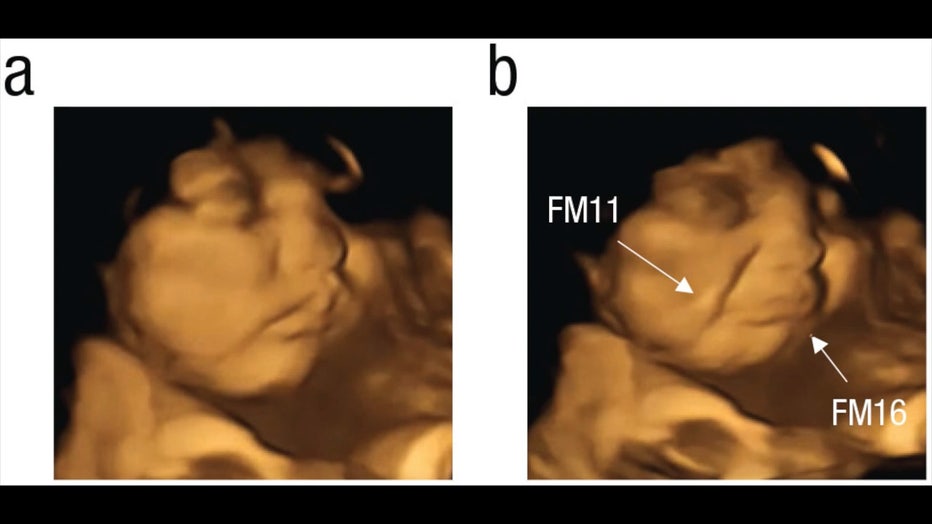

Fetus-kale.jpg

4D ultrasound scan showing before and after result after pregnant woman ingests kale capsule. (Beyza Ustun, Nadja Reissland, Judith Covey, Benoist Schaal, and Jacqueline Blissett via Storyful)

The fetuses exposed to the carrot capsule showed a more "laughter-face" expression, and the ones exposed to the kale capsules showed a more "crying-face" expression, according to researchers.